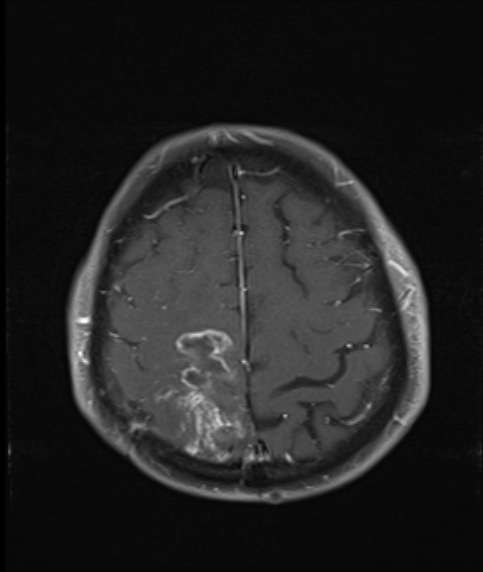

Bazı vakalarda tümör çıkartılamaz. Böyle durumlarda cerrah sadece biyopsi yapar ve tümörün küçük bir kısmını çıkartır. Çıkan kısım patolojiye yollanır ve mikroskop altında incelenerek kesin tipi öğrenilir. Bu tedavinin şekillendirilmesinde önemli bir bilgi kaynağıdır. Biyopsi açık cerrahi ile yapılabildiği gibi genel durumu buna izin vermeyen hastalarda özel sistemler kullanılarak bir iğneyle de yapılabilir. Doktor hastanın başına özel bir çerçeve (Frame) takarak MR ve/veya BT görüntüleri alır. Bu şekilde tümör dokusunun kafa içindeki kesin yerleşim yeri koordinatları ile belirlenir. Bu bilgilerle kafa tasına küçük bir delik açılarak biyopsi iğnesi doğrudan tümöre hedeflenir ve biyopsi alınır. Bu tekniğe stereotaksi denilir.

Bu tedavi şekillerinden birisi ile tedavisi yapılan hastalar, süresi doktorlar tarafından belirlenen ve ilk başlarda daha sık; sonra araları açılan kontrollere gelirler. Kontroller sırasında BT veya MR görüntüleri ile tümördeki değişimler takip edilir, hastaların tam bir muayenesi yapılır. Gerek görülürse ilaç tedavileri düzenlenir.